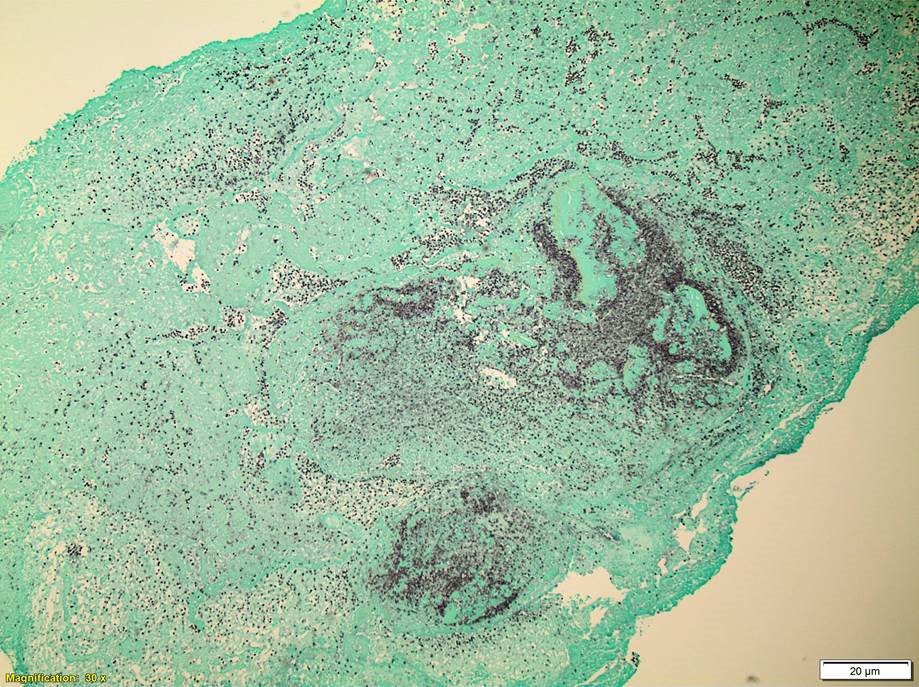

Ampicillin or vancomycin are acceptable treatment options for Enterococcal infections if found to be susceptible by antibiotic testing. It is important to note, Enterococcus spp. are intrinsically resistant to cephalosporins, aminoglycosides, trimethoprim-sulfamethoxazole, and clindamycin. For serious infections, including infective endocarditis, it is recommended to treat with a cell wall active agent such as ampicillin and an aminoglycoside (gentamicin or streptomycin) to create a synergistic bactericidal effect. Emergence of E. faecium acquired vancomycin resistance (VanA/VanB) is increasing and more board spectrum agents such as daptomycin and linezolid are necessary to effectively treat these infections. In the case of our patient, upon identification of E. faecalis from multiple blood cultures, his antibiotics were switched to IV ampicillin and gentamicin. He underwent valve replacement surgery and both the aortic and mitral valves grew E.faecalis as well and showed numerous bacterial cocci on histology (Images 3 & 4). He completed a six week course of ampicillin and gentamicin and was discharged home in good condition.